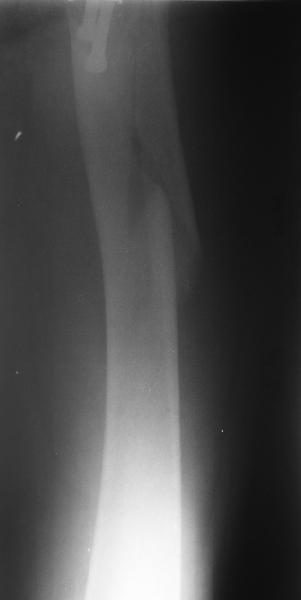

1LateralAnother lateral

Женшина 69 лет оперирована у нас 2 года назад по поводу перелома шейки. Ходила дома без дополнительной опоры, на улице - с тростью.Сегодня утром села мимо табуретки. Поскольку наша бывшая пациентка, сегодня же из области родственники привезли к нам. Картинка в приложении. Какие будут предложения по тактике?

Regarding this specific patient, it is quite difficult for me to discern the exact fracture pattern and therefore treatment suggestions. It appears to be a spiral fracture starting just proximal to the less trochanter and extending distally 6 or more cm into the shaft with medial displacement of the distal fragment. The lesser troch is a seperate fragment. The 2 year old femoral neck fracture appears to have healed in good position I really can't tell where the fracture starts laterally, but presumably it's near the distal most screw.

I can't tell if there is further comminution of the shaft or the greater trochanter. I can barely see the fracture on the lateral radiograph. I'm not sure but I don't see AVN of the femoral head nor OA of the hip. Her overall bone quality appears normal for a 68 year old. I don't see any loosening of the screws but I can't tell for sure.